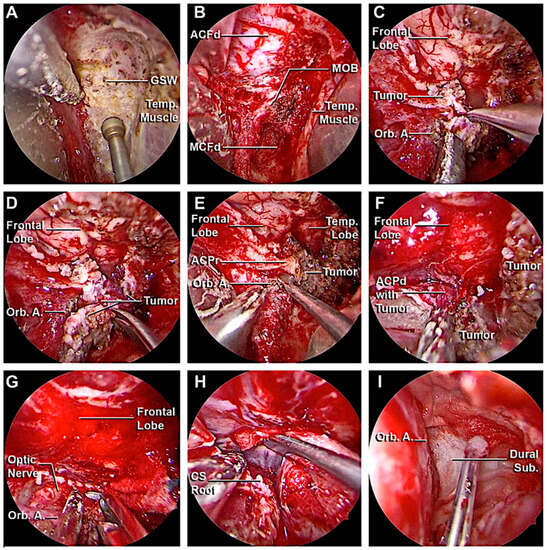

3.3.1. Case 1